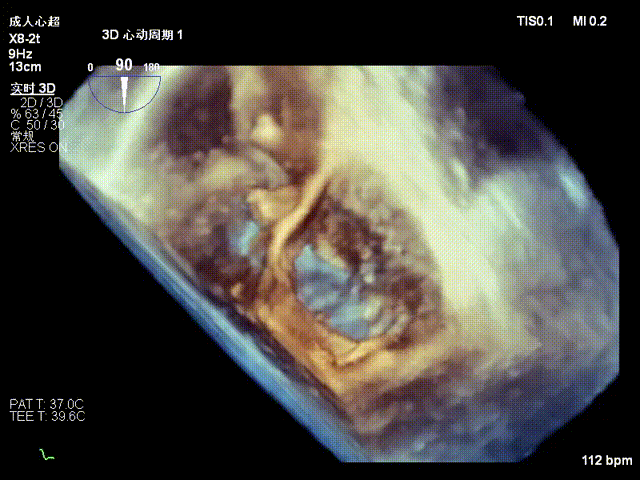

One 14T K-Clip® was implanted at the junction of the posterior and septal annuli of the patient's tricuspid valve, and one 16T K-Clip® was implanted at the junction of the posterior and anterior annuli. The overall annular area was reduced by 45%. Leaflet coaptation was improved, and regurgitation was effectively reduced from severe preoperative to moderate. The overall surgical outcome exceeded expectations, and the procedure was successfully completed.

After implantation of two clips, the annulus area is 11.8 cm²

Postoperative regurgitation